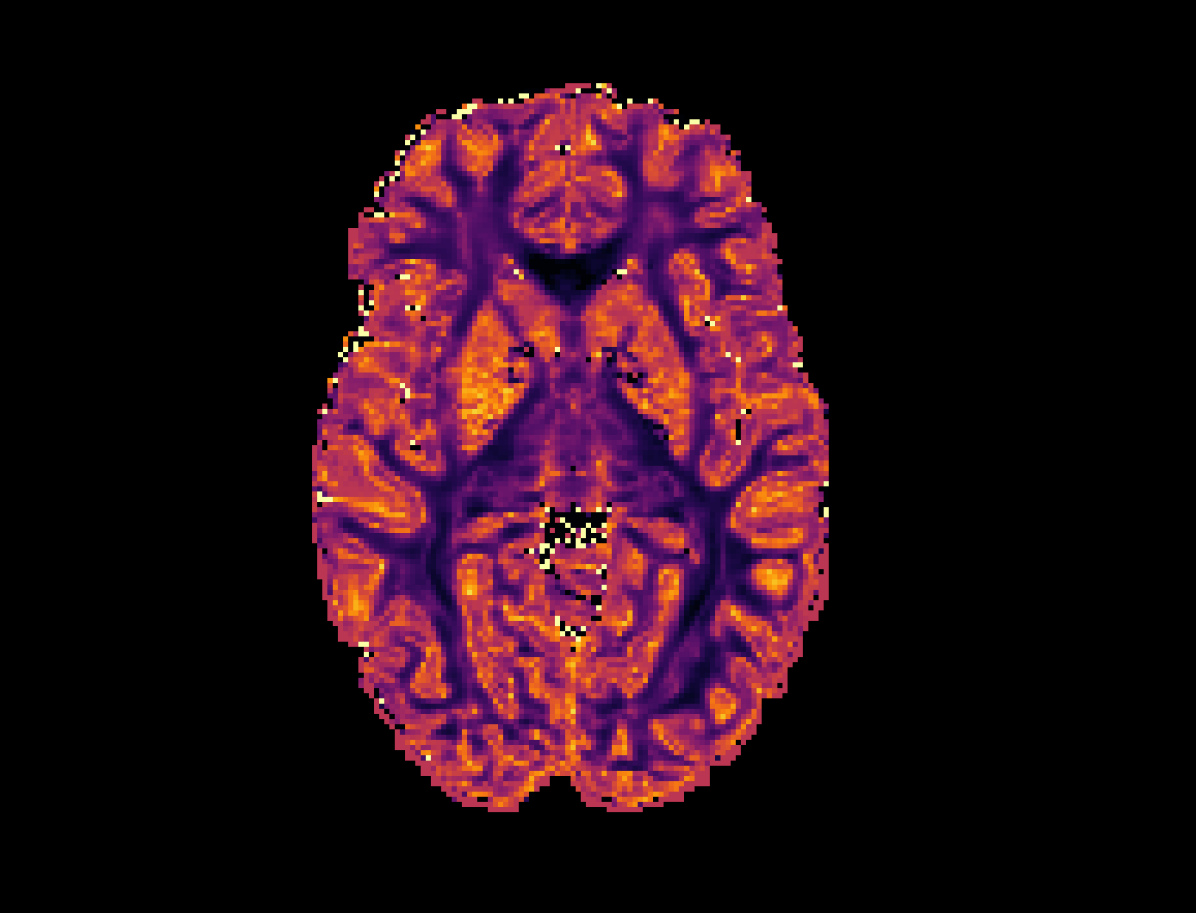

Refer to caption

(a) High Resolution

(b) SR-q-DL

(c) RCNN

Refer to captionRefer to caption

(d) PCCNN-Bv

Figure 4: Axial slice of orientation dispersion index (OD) within one subject across different models. Models use single-shell data (b=1000s/mm2𝑏1000ssuperscriptmm2b=1000\mathrm{s/mm^{2}}) with angular dimension size qin=10subscript𝑞in10q_{\mathrm{in}}=10 as input, and produce 808080 b=1000s/mm2𝑏1000ssuperscriptmm2b=1000\mathrm{s/mm^{2}}, 909090 b=2000s/mm2𝑏2000ssuperscriptmm2b=2000\mathrm{s/mm^{2}}, and 909090 b=3000s/mm2𝑏3000ssuperscriptmm2b=3000\mathrm{s/mm^{2}} inferred volumes.